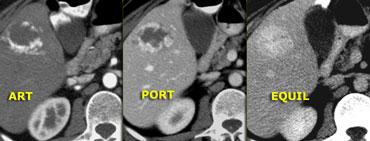

Bên trái là tổn thương giảm âm không điển hình, được bao quanh bởi một quầng sáng nhỏ nhưng rõ ràng.

Trong pha động mạch, có ngấm thuốc đồng nhất với cường độ động mạch, thường gặp trong u máu nhỏ.

Trong pha tĩnh mạch cửa và pha cân bằng, tổn thương có cùng mức độ ngấm thuốc như động mạch chủ.

Như vậy, tất cả các đặc điểm đều phù hợp với u máu, một tổn thương mạch máu lành tính, không phải tổn thương đặc.